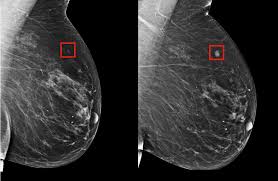

Ductal carcinoma in situ (dcis) is the presence of abnormal cells inside a milk duct in the breast. A mild type of lymphedema can occur within a few days after surgery and usually lasts a short time. Advanced stage 4 symptoms may include: Learn more about the symptoms and diagnosis of breast cancer. A blood test can pick up cancers up to four years before symptoms appear, researchers say, in the latest study to raise hopes of early detection. Turns out, there was another in the other breast that didn't show up on a mammogram. 93 percent for stage 2. Since the majority of studies have found the average doubling time to be between 50 days and 200 days, it's likely that most breast cancers that are diagnosed began at least 5 years earlier (but again, this is assuming that growth rate is constant which it is not). Inflammatory breast cancer (ibc) is a rare and aggressive form of breast cancer that often appears as a rash or an irritated area of skin. In this situation, the breast cancer has already spread to the other parts of the body such as the lung. 1 when can breast cancer first be detected? Some warning signs of breast cancer are— new lump in the breast or underarm (armpit). Tumors may be as small as the tip of a pencil (1 mm) or as big as a lime (50 mm).

Learn more about the symptoms and diagnosis of breast cancer that has spread to the lung. A sign, such as fever or bleeding, can be seen or measured by someone else. Dcis is usually found during a mammogram done as part of breast cancer screening or. 1 when can breast cancer first be detected? Learn more about the symptoms and diagnosis of breast cancer. A cough that persists for more than two weeks, especially a dry cough, can be a sign of lung cancer. Some people may describe the pain as a burning sensation. Signs and symptoms of cancer depend on where the cancer is, how big it is, and how much it affects nearby organs or tissues. The cancer may come back in the same place as the original cancer (local recurrence), or it may spread to other areas of your body (distant recurrence). Thickening or swelling of part of the breast. But there is a rare type of breast cancer that can cause a dry, red, itchy rash to appear on or around your nipples, similar to the type you get with eczema, she explains. That's because they're often diagnosed early on, before symptoms develop. There are several types of lymphedema: